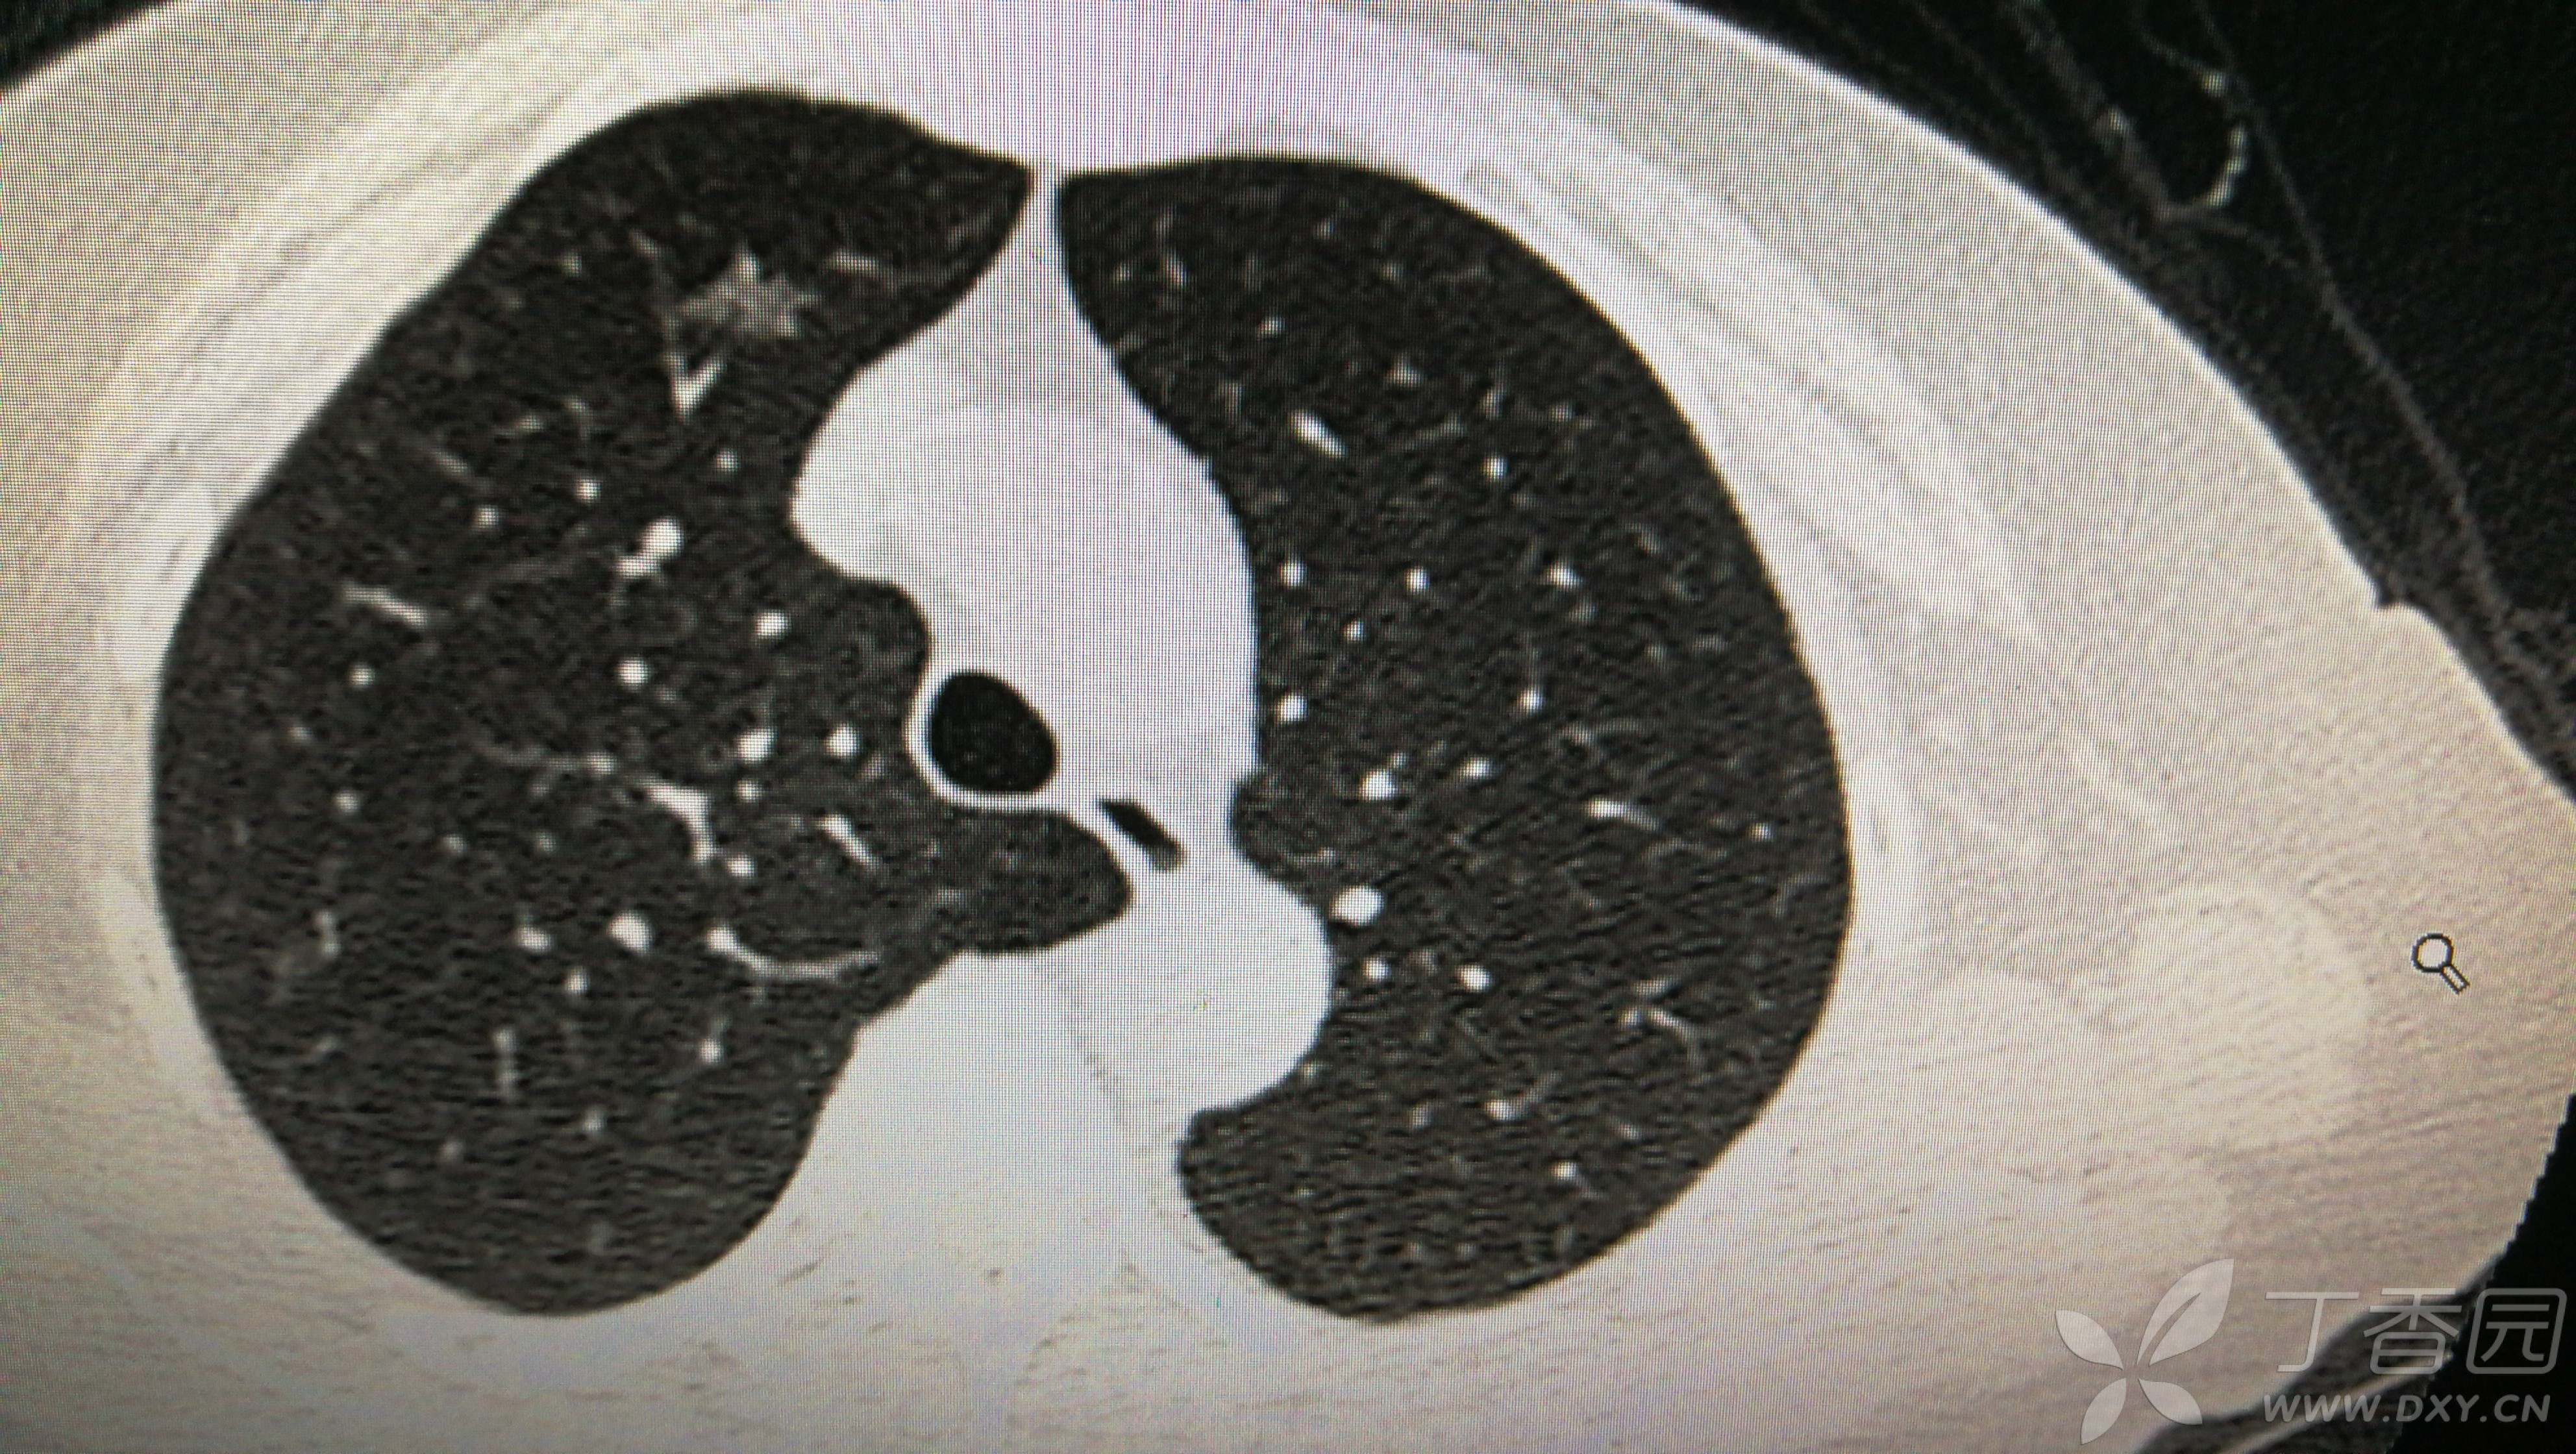

①双肺多发磨玻璃结节

②右下肺实性结节